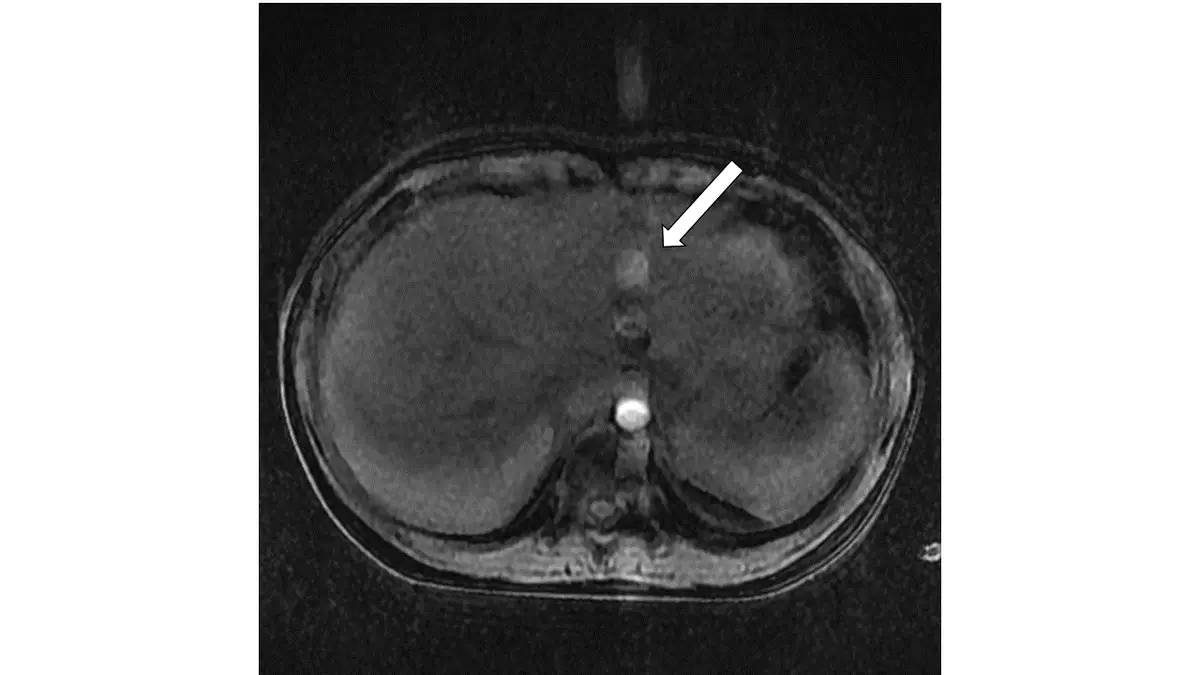

磁振造影檢查呈現如下圖,下列有關箭號所指之敘述何者最正確? 圖片

本圖為腹部 MRI 橫切面影像,可見右側肝臟和左側脾臟。白色箭頭指向椎體前方、主動脈旁一個高訊號(bright signal)的圓形影,位置緊鄰主動脈。此影像特點如下:

• 位置:在相位編碼(phase encoding)方向上,與主動脈形成一定間隔的高訊號影

• 形態:邊緣清晰,形狀規則,與主動脈本身的訊號特性相似

• 機制:主動脈血流為搏動性(pulsatile flow),血流在不同心動週期階段有不同的相位偏移,導致相位編碼方向產生規則間隔的鬼影(ghost image)。此現象稱為 flow artifact 或 phase-encoded motion artifact

• 鑑別要點:真正的肝臟腫瘤或膽結石不會出現在血管旁並呈現此種規則性高訊號模式;aliasing 假影(折返假影)則表現為影像在 FOV 邊緣折回,形態不同